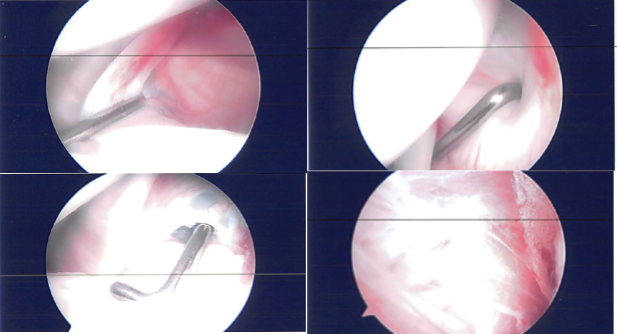

A general anesthesia induced and patient was put in lateral decubitus and position with bean bag in place. The left shoulder was prepped and draped aseptically in a usual fashion. The left arm was put into flexion and abduction on a post. Pre-draping examination under anesthesia was done and found to have no instability or subluxation.

A posterior portal, entry portal was made of the shoulder. The scope was entered into the glenohumeral joint. Examination of the glenohumeral joint was done and found to have some fraying of the articular surface of the rotator cuff as well as fraying of the anterior superior glenoid labrum and deep to the biceps tendon.

The biceps tendon was intact. The IGHL, MGHL, subscapularis, inferior and posterior labrum were intact. Pictures were taken and saved.

Debridement of the glenoid labrum and rotator cuff were performed using a shaver. The closure was done using nylon. Dressing was performed. The left arm was put in a shoulder sling and the patient was extubated and moved to the recovery unit in a stable condition.